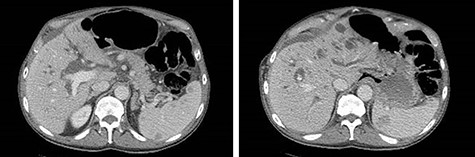

A 74-year-old male with past medical history of hypertension, coronary artery disease and prostatectomy, presented with jaundice, weight loss and abdominal pain. Initial cross-sectional imaging revealed biliary ductal dilation and a stricture of the pancreatic portion of the common bile duct (Fig. 1). Endoscopic retrograde cholangiopancreatography was performed, at which time biopsy was nondiagnostic. After a 6-week delay, the patient underwent PD for presumed malignancy, with final pathology revealing moderately differentiated invasive pancreatic adenocarcinoma, T2N1, with 2 of 22 lymph nodes involved, and negative margins. Of note, the right colon was mobilized from its lateral attachments and the afferent biliopancreatic jejunal limb was passed through the transverse mesocolon to the right of the middle colic vessels. Postoperatively, the patient completed 6 months of adjuvant chemotherapy with FOLFIRINOX. There was no evidence of recurrence on surveillance imaging.

CT of the abdomen and pelvis demonstrating severe intrahepatic and extrahepatic biliary ductal dilation and multiple splenic hemangiomas.